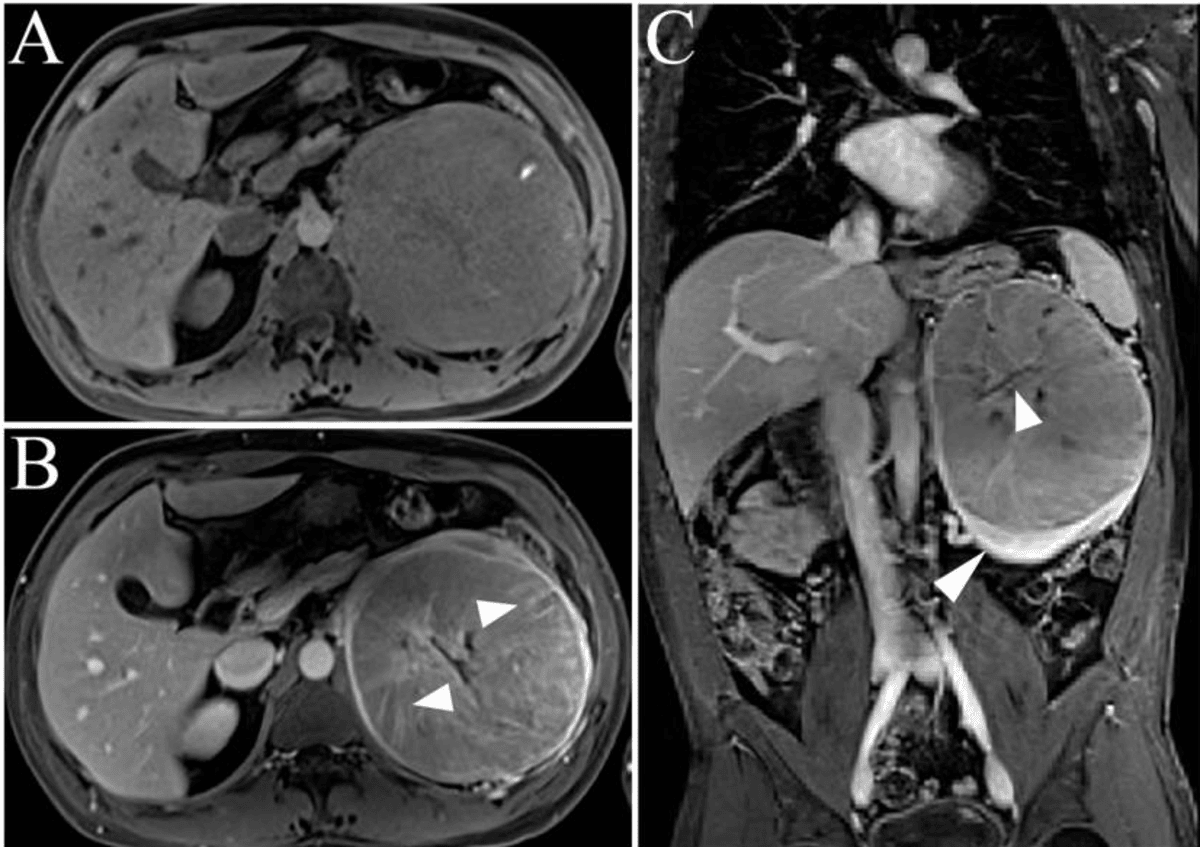

MRI can show the loss of the normal bright fat plane around the kidney, suggesting that the tumour has invaded the surrounding (perinephric) fat36. This finding upstages the disease to at least T3a and has important implications for surgical planning and prognosis.

MRI excels at following tumour-related clot (tumour-thrombus) extending from the renal vein into larger vessels, such as the inferior vena cava (IVC) and even the right atrium of the heart39. Visualising the entire course of such a thrombus is critical for operative strategy and risk assessment.

MRI assesses whether the tumour has come into contact with or invaded organs near the kidney, such as the psoas muscle, colon, or liver41. Involvement of these structures can alter surgical plans, potentially requiring more extensive or multidisciplinary intervention.